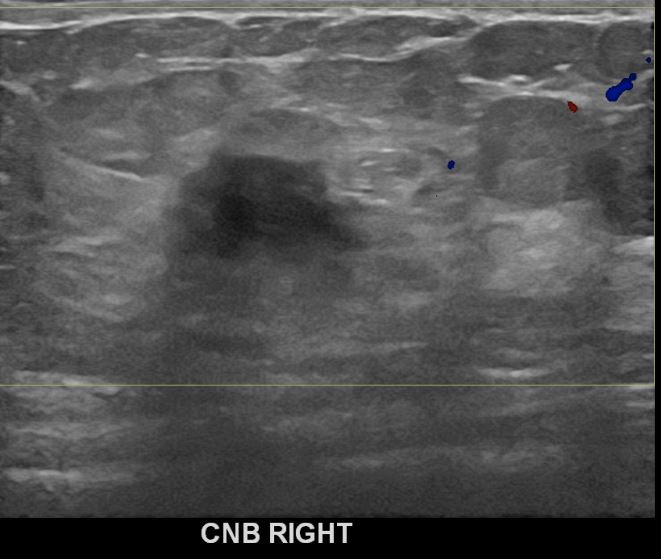

상기환자 외부검사상 이상소견으로 내원하신 50대여성으로 우측 유방의 의심스러혹

조직검사시행해 유방암 진단되었읍니다